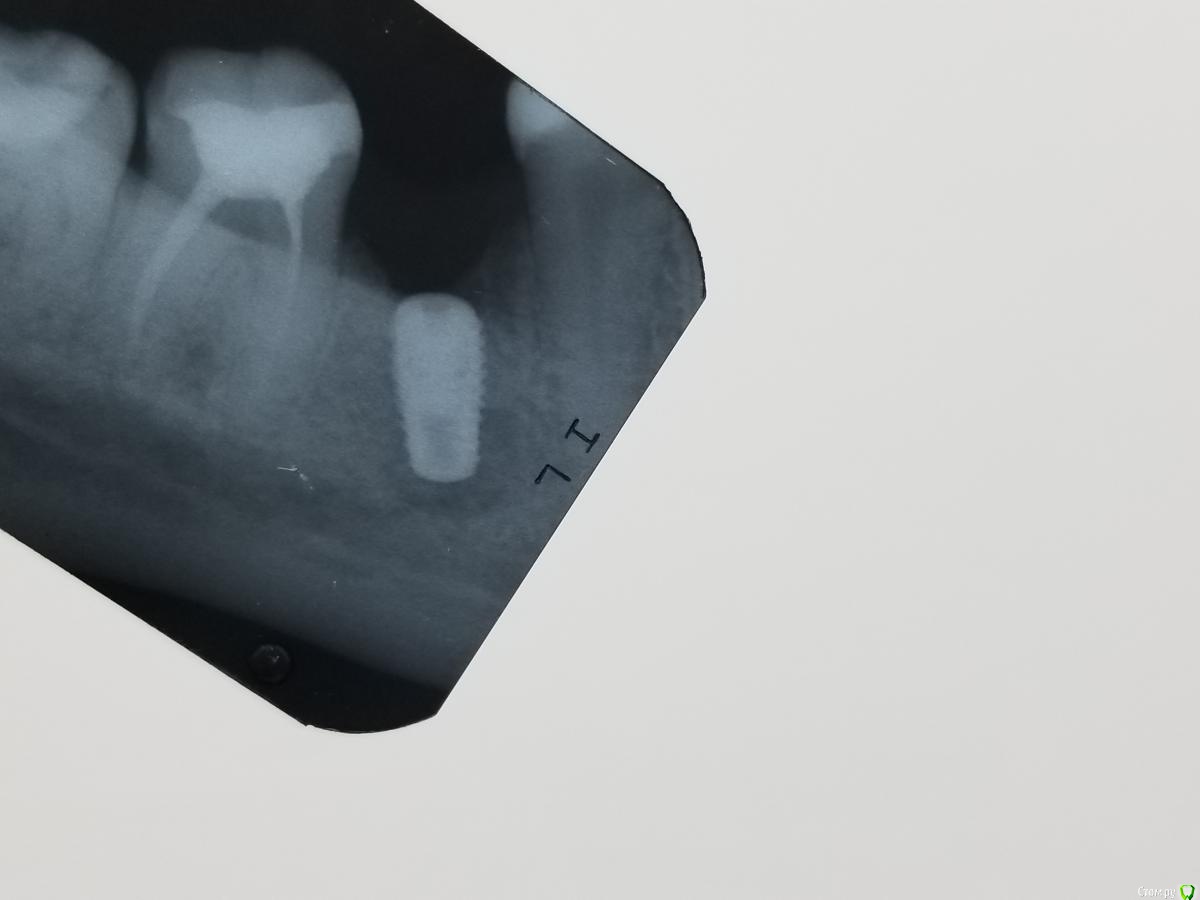

Большой Зеленый Опубликовано 10 февраля, 2019 Поделиться Опубликовано 10 февраля, 2019 Острый верхушечный периимплантит)) 1 Ссылка на комментарий

АнтонТЛТ Опубликовано 10 февраля, 2019 Поделиться Опубликовано 10 февраля, 2019 (изменено) Не знаю, в чем причина. Наука говорит, что единственная причина - инфекция. Хотя при санации очага содержимое не походило на грануляции. Еще определялось сообщения очага с резцовым каналом, может дремлющая киста канала напала на имплант..)))Наука говорит, что перегрев является причиной верхушечного периимплантита))Для препарирования ложа под длинные имплантаты рекомендовано использовать внутреннюю ирригацию) Изменено 10 февраля, 2019 пользователем АнтонТЛТ 2 Ссылка на комментарий

Kostoprav Опубликовано 10 февраля, 2019 Поделиться Опубликовано 10 февраля, 2019 Подобная хрень тоже случалась. Возможно перегрев, хотя препарирую всегда с охлаждением Ссылка на комментарий

AlexanderGudkov Опубликовано 10 февраля, 2019 Автор Поделиться Опубликовано 10 февраля, 2019 Наука говорит, что перегрев является причиной верхушечного периимплантита))Для препарирования ложа под длинные имплантаты рекомендовано использовать внутреннюю ирригацию)Самая последняя наука говорит, что перегрев - не причина)) Ссылка на комментарий